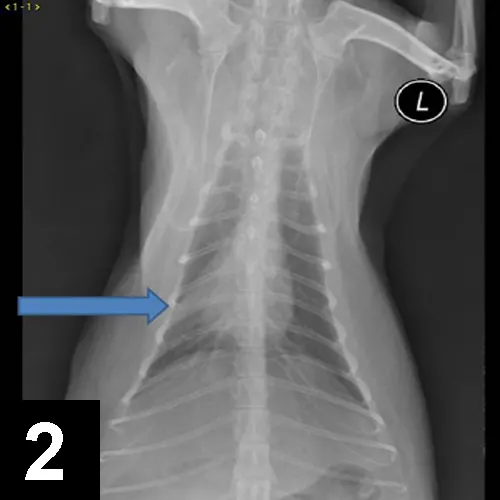

Luna was placed in an oxygen-enriched cage, and thoracic radiographs (Figure 1) were taken.

Figure 1. Thoracic radiographs taken at presentation.

Luna’s clinical signs and radiograph findings were most consistent with lower airway disease (ie, feline asthma). While asthma implies reversible bronchoconstriction, some cats with lower airway disease have more inflammatory changes and less reversible airway changes.

Radiographic findings consistent with airway disease include donuts and tram lines, which are supportive of bronchial thickening and hyper­inflation from expiratory flow limitation. Some cats with lower airway disease also have a collapsed middle lung lobe (Figure 2).